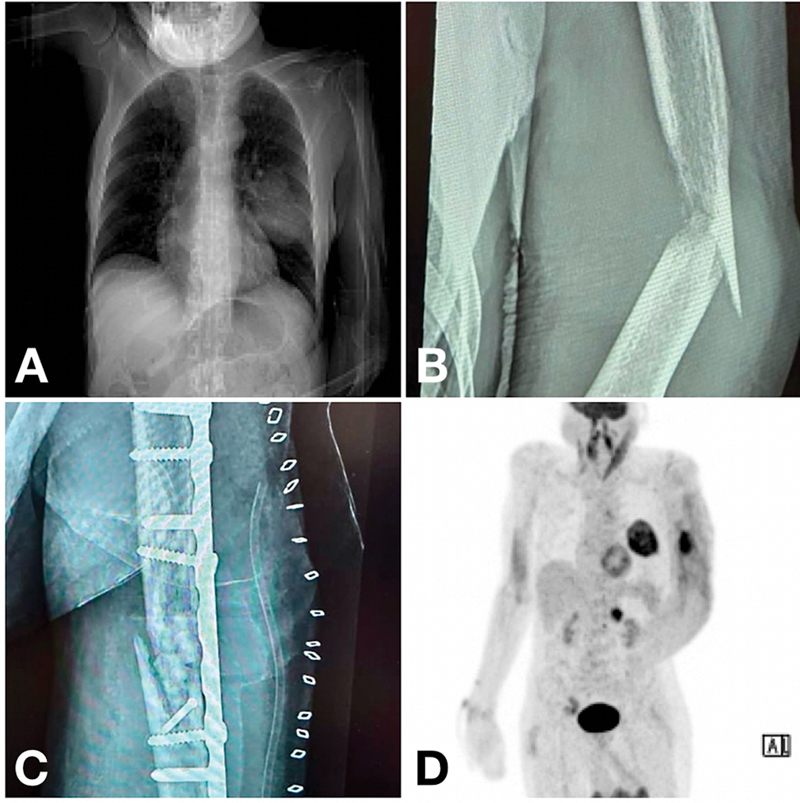

An 88-year-old man presented with a fracture of the left humerus following a trivial trauma. There was no relevant history or comorbidities. He was planned for open reduction and internal fixation. On preoperative evaluation, a suspicious, well-defined radio-opaque lesion was noted in the left mid-zone of the lung on chest X-ray and computed tomography (CT) of the thorax ([Fig. 1A]). Intraoperatively, a solid lesion was noticed around the fracture site in the adjacent soft tissue ([Fig. 1B]). A biopsy was performed, and left humerus bone tissue with surrounding soft tissue was sent for histopathological examination following fracture fixation ([Fig. 1C]). The preoperative X-ray, CT picture, and intraoperative findings were consolidated, and positron emission tomography CT (PET-CT) was advised for further evaluation. PET-CT revealed left lung malignancy with mediastinal lymph node and adrenal and bone metastasis ([Fig. 1D]). On histopathological examination, the tumor cells were arranged in sheets and nests. Individual cells showed round to polygonal cells with nuclear pleomorphism, increased nuclear to cytoplasmic ratio, moderate eosinophilic cytoplasm, vesicular chromatin with prominent nucleoli admixed with numerous multinucleated giant cells, and areas of necrosis within the nests ([Fig. 2A, B]). The differentials were metastatic adenocarcinoma and malignant giant cell lesions of the bone. To establish the primary origin of the tumor, a panel of markers was performed by immunohistochemistry (IHC). Surprisingly, IHC showed cytoplasmic and membranous positivity for CK7 only and negative for other markers like TTF1, napsin A for primary lung adenocarcinoma, P63 for giant cell tumor of bone, CK20 for lower gastrointestinal tract neoplasms, inhibin for adrenal cortical tumor, and NKX3.3 for prostate adenocarcinoma ([Fig. 2C, D]). However, due to patients economic constraints only a limited panel of IHCs were indicated, CD68 to confirm osteoclast-like giant cells (OGC) and molecular profiling could not be performed. Collaborating the radiological findings with histopathological and IHC features, on literature search, it was identified that non-small-cell lung carcinoma with OCG (NSCLC-OCG) is a relatively rare entity that may be negative for primary lung markers and can present upfront with metastasis, masking the primary site of origin and making diagnosis more intriguing. Since the patient was an elderly, curative treatment was deemed inappropriate and palliative care was given. Subsequently, the patient died within 3 months of diagnosis.

Fig 1: (A) X-ray chest: lesion in the mid-zone of the left lung. (B) X-ray: Fracture of the left humerus following a trivial trauma. (C) Postoperative X-ray. (D) PET-CTwith fluorodeoxyglucose (FDG): avid lesion in the left lung, mediastinal lymph nodes, left adrenal gland, and left humerus.